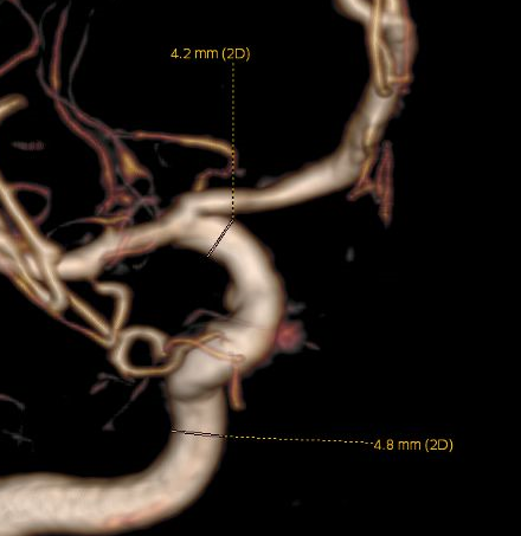

左侧瘤体形态欠规则,4mm×30mm Streamline 优先处理左侧动脉瘤

术后3月复查,瘤体未见显影,载瘤动脉通畅

同期4mm×20mm Streamline 进一步处理右侧动脉瘤